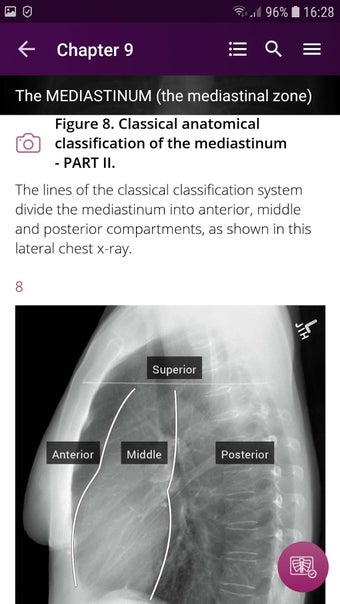

Radioloji'yi Keşfet: Göğüs Röntgeni Yorumlama, göğüs röntgeninin yorumlanmasının anlaşılmasını artırmak için tasarlanmış bir eğitim uygulamasıdır ve doktorlar, tıp öğrencileri ve radyologlar tarafından kullanılması amaçlanmaktadır. Uygulama, en küçük detayları görüntülemek için yakınlaştırılabilecek yüksek kaliteli görüntüler ve her bulgunun önemini anlamanıza yardımcı olacak bir sesli yorum içerir.

Uygulamanın amacı, kullanıcıların farklı x-ışını bulgularını ve bunların bir hastalığın teşhisinde nasıl kullanılabileceğini daha iyi anlamalarına yardımcı olmaktır. Uygulama, göğüs röntgeni yorumlaması için gerekli çeşitli yapı taşlarını kapsayan 5 bölüme ayrılmıştır.